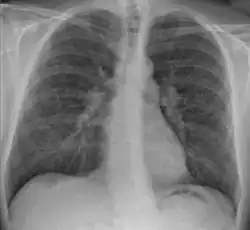

-

Hilar adenopathy especially on the person's left (AP CXR) -

Hilar adenopathy especially on the person's left (lateral CXR) -

Hilar adenopathy especially on the person's left (coronal CT) -

Hilar adenopathy especially on the person's left (transverse CT)